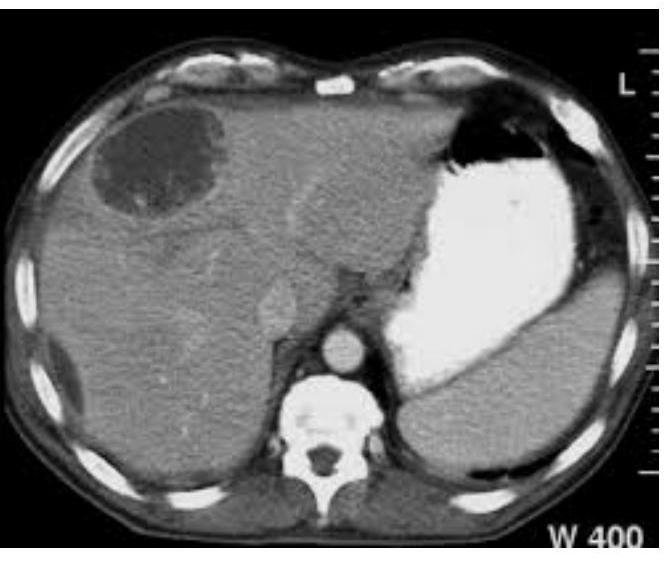

# ABSCESO HEPÁTICO ## DEFINICIÓN Es una necrosis enzimática de los hepatocitos y múltiples microabscesos que confluyen, formando habitualmente cavidad única, conteniendo líquido homogéneo que puede variar en color, desde la crema blanca hasta el de "pasta de anchoas". ## ABSCESO HEPÁTICO AMEBIANO Es la manifestación extraintestinal más frecuente de la infección por *Entamoeba histolytica*. Causada por la ingesta de quistes en el agua o alimentos contaminados. Pudiendo tener antecedente de **disentería amebiana**. ## ABSCESO HEPÁTICO PIÓGENO Es el absceso hepático más frecuente de etiología por colangitis ascendente, criptogénico, vía portal o arterial por algún **foco séptico**, por contigüidad (colecistitis o peritonitis). ## EPIDEMIOLOGÍA - La amebiasis es la segunda causa de muerte por enfermedad parasitaria en todo el mundo. - El parásito causante es un patógeno potente, posee proteasas secretoras que disuelven los tejidos del huésped, matando por contacto a las células y fagocitando a los eritrocitos. | FACTORES DE RIESGO AMEBIANO | FACTORES DE RIESGO PIÓGENO | | :------------------------------------------------------------------------------------------------------------------------ | :----------------------------------- | | - Sexo masculino - 3^{\circ} a 5^{\circ} década de la vida - Alcoholismo - Padecimientos oncológicos - Prácticas homosexuales - Inmunosupresión - Habitar o viajar a **zonas endémicas** - Uso de corticosteroides | - Presencia de **foco infeccioso** - Mayores de 50 años | # CLÍNICA | ABSCESO AMEBIANO | ABSCESO PIÓGENO | | :------------------------------------------------------------------------------------------------------------- | :----------------------------------------------------------------------------------------- | | - Fiebre vespertina o nocturna no muy alta. - Dolor en hipocondrio derecho - Hepatomegalia - **Ictericia** - Escalofríos y malestar general. (puede haber antecedente de disentería) - **Amebomas**: masas ileocecales en CSD | - Fiebre aguda en picos - Dolor en hipocondrio derecho - **Ictericia** - Vómitos - Anorexia - Mialgias y malestar general (puede haber **choque séptico**) | ## DIAGNÓSTICO ## GOLD STANDARD: USG DE HÍGADO Y VÍAS BILIARES - Es el estudio de elección ante la sospecha de un absceso hepático de cualquiera de sus etiologías. - Colección única en **lóbulo hepático derecho** sugiere origen amebiano (80%). ## PUNCIÓN GUIADA POR USG O TAC - Se realiza cultivo del aspirado del absceso para llegar a un diagnóstico etiológico definitivo.   # TRATAMIENTO ## ABSCESO AMEBIANO ## 1ª elección: **Metronidazol + Amebicida intraluminal** (Furoato de Diloxanida, Paromomicina). ## 2ª elección: Si hay intolerancia a Metronidazol - **Tinidazol**. Si hay intolerancia a Imidazoles - **Nitazoxanida**. ## PUNCIÓN PERCUTÁNEA - Persistencia de síntomas clínicos de 72 horas de iniciado el tratamiento. - Datos de **ruptura inminente**. - Absceso de **lóbulo hepático izquierdo**. - Embarazo y contraindicación del uso de Metronidazol. - Complicaciones pleuropulmonares (absceso que se va a pleura). ## ABORDAJE LAPAROSCÓPICO - Drenaje por esta vía si hay **fracaso** en el percutáneo. ABORDAJE LAPAROTOMÍA - En caso de **ruptura** del absceso a cavidad peritoneal. ## ABSCESO PIÓGENO 1ª elección: **Antibiótico de amplio espectro + Drenaje percutáneo**. Esto debe indicarse en **TODOS** los casos. Elegir el antibiótico con base en la etiología más frecuente del foco séptico responsable. El drenaje percutáneo también deberá servir para descomprimir la vía biliar. ## DRENAJE QUIRÚRGICO - Absceso **múltiple**. - **Multiloculado**. - **Foco infeccioso** que requiere cirugía. - Si el drenaje no es posible por su localización (**superior o posterior**). # PRONÓSTICO ## MORTALIDAD | ABSCESO AMEBIANO | ABSCESO PIÓGENO | | :------------------------------------------------- | :-------------- | | 1 % | 20 % | | Complicación más frecuente - **Lesión pleuropulmonar**. | | ## FACTORES DE MAL PRONÓSTICO - Abscesos **múltiples**. - Volumen **>500 ml**. - Elevación del **hemidiafragma derecho** (o derrame pleural). - **Encefalopatía**. - Bilirrubina **>3.5 mg/dL**. - Hemoglobina **<8 mg/dL**. - Albúmina **<2 g/dL**. - **Diabetes mellitus**. ## REFERENCIA Enviar a **segundo nivel** si hay sospecha de absceso amebiano.